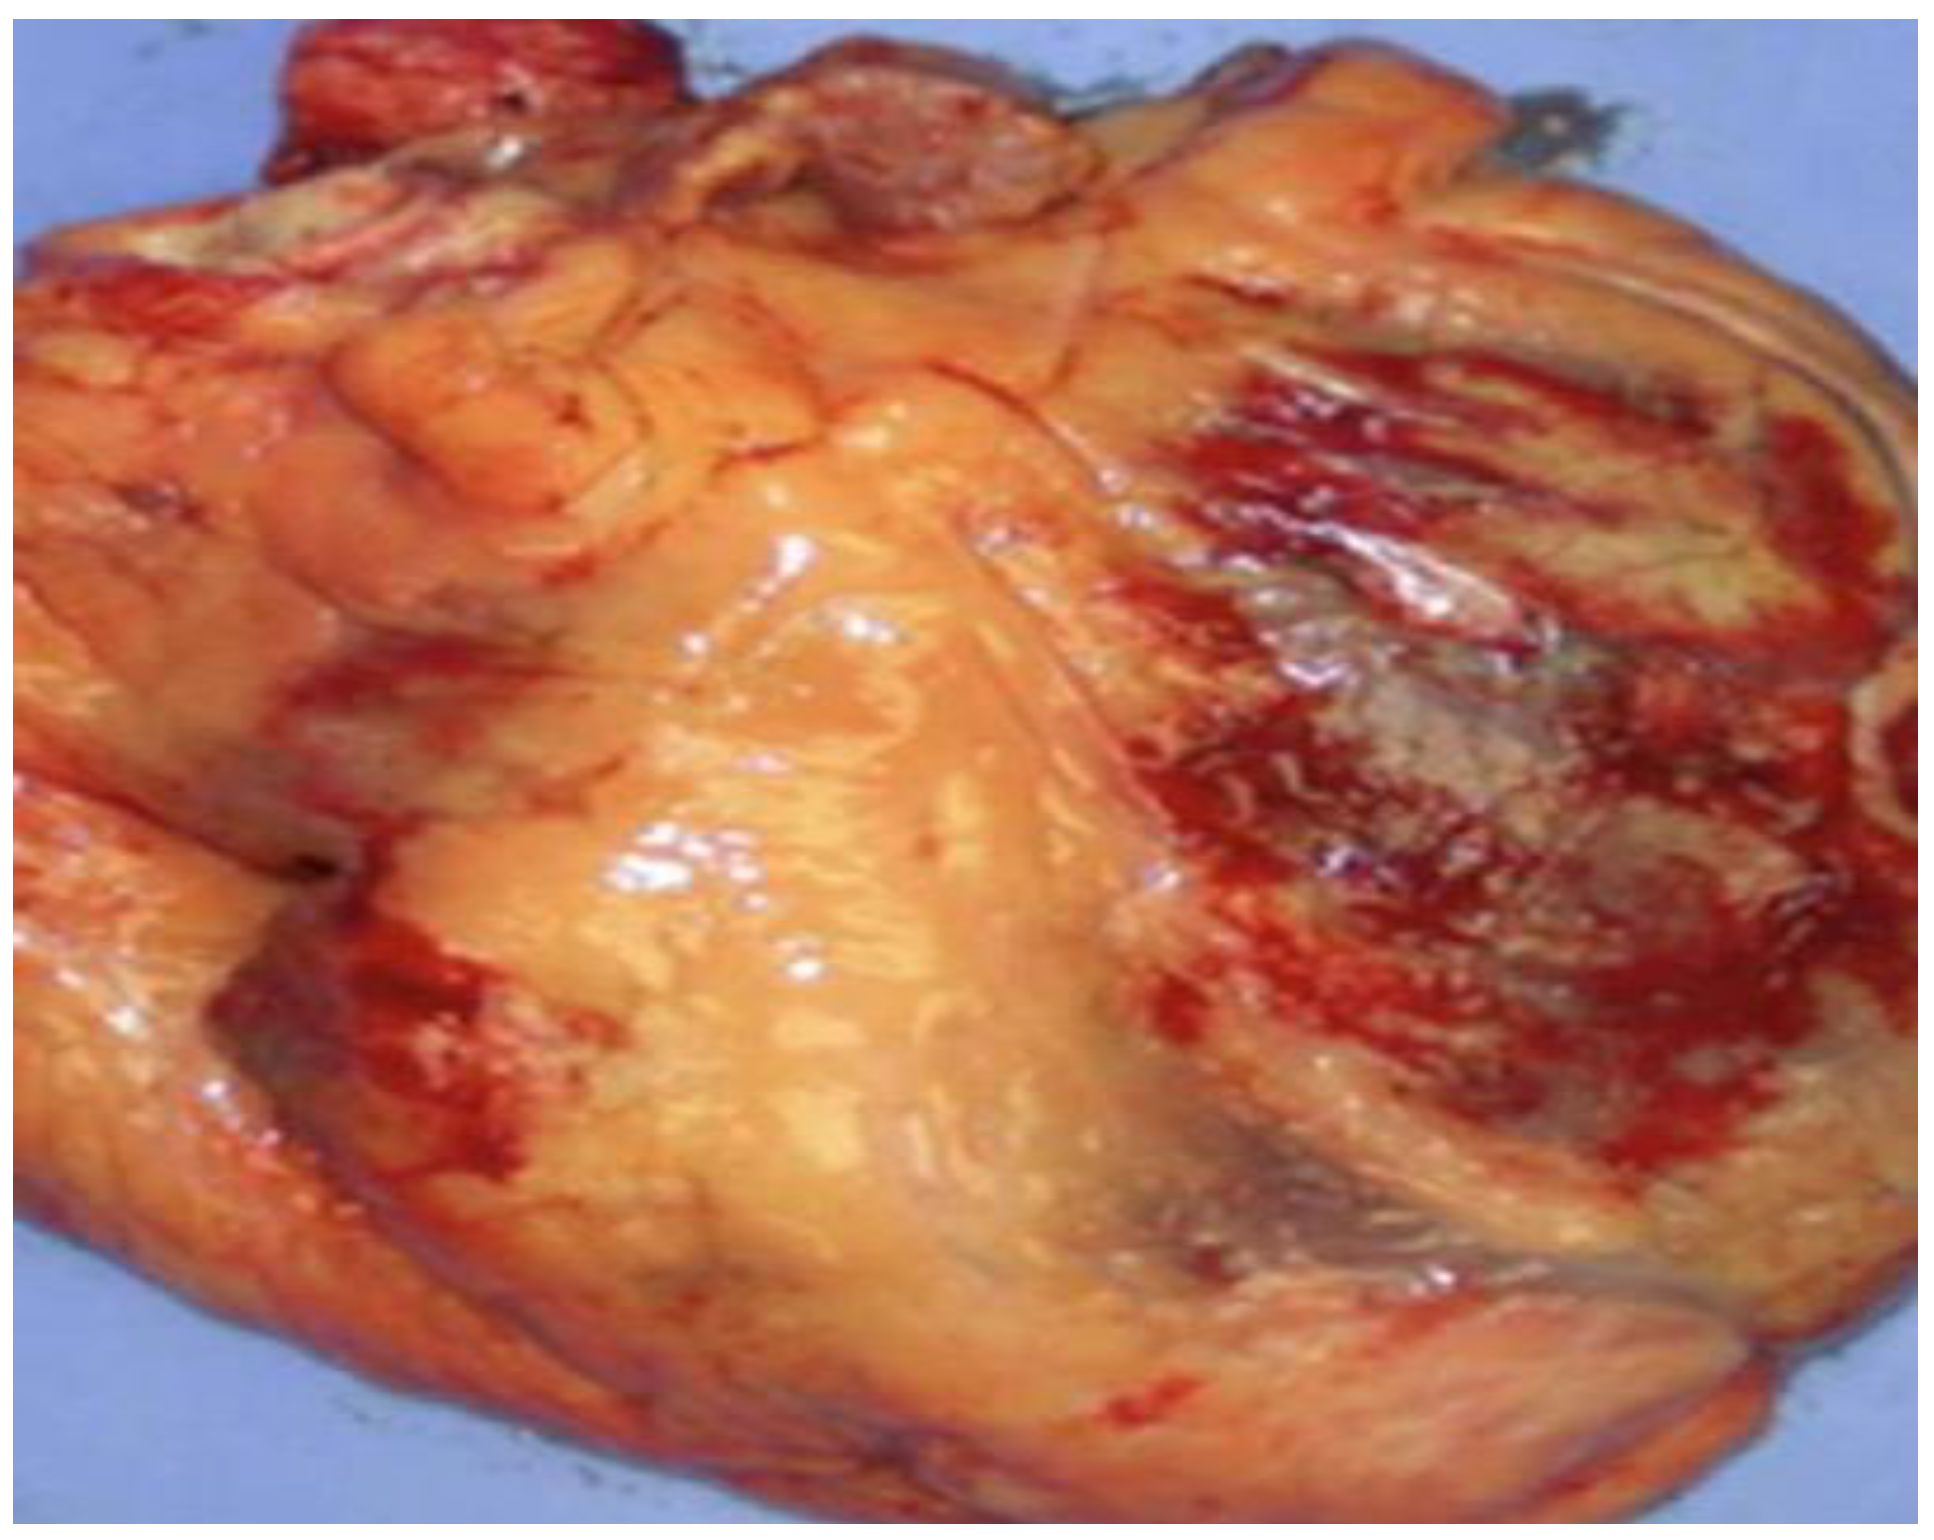

| Deshpande et al., 2016 [112] | Patients: 16 ARVC/D pediatric patients. Histopathologic observations: 6 autopsies, 6 explanted hearts, and 3 biopsies revealed massive fibro-fatty infiltration in the RV. Genetic observations: Two patients presented mutations previously reported and only one had a novel mutation of a known ARVC/D gene. |